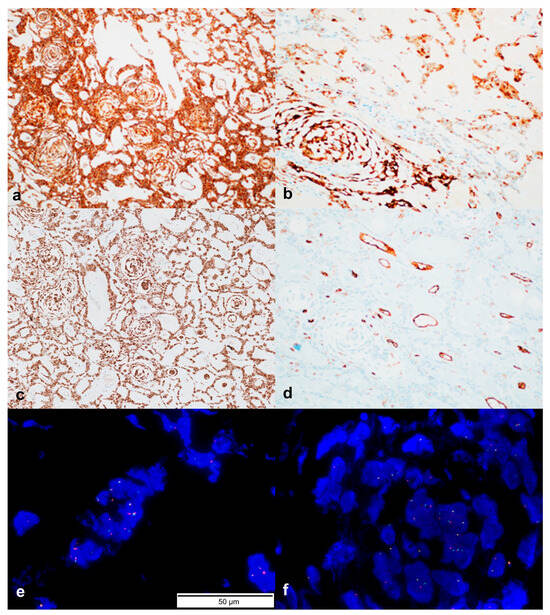

3.3. Immunohistochemistry